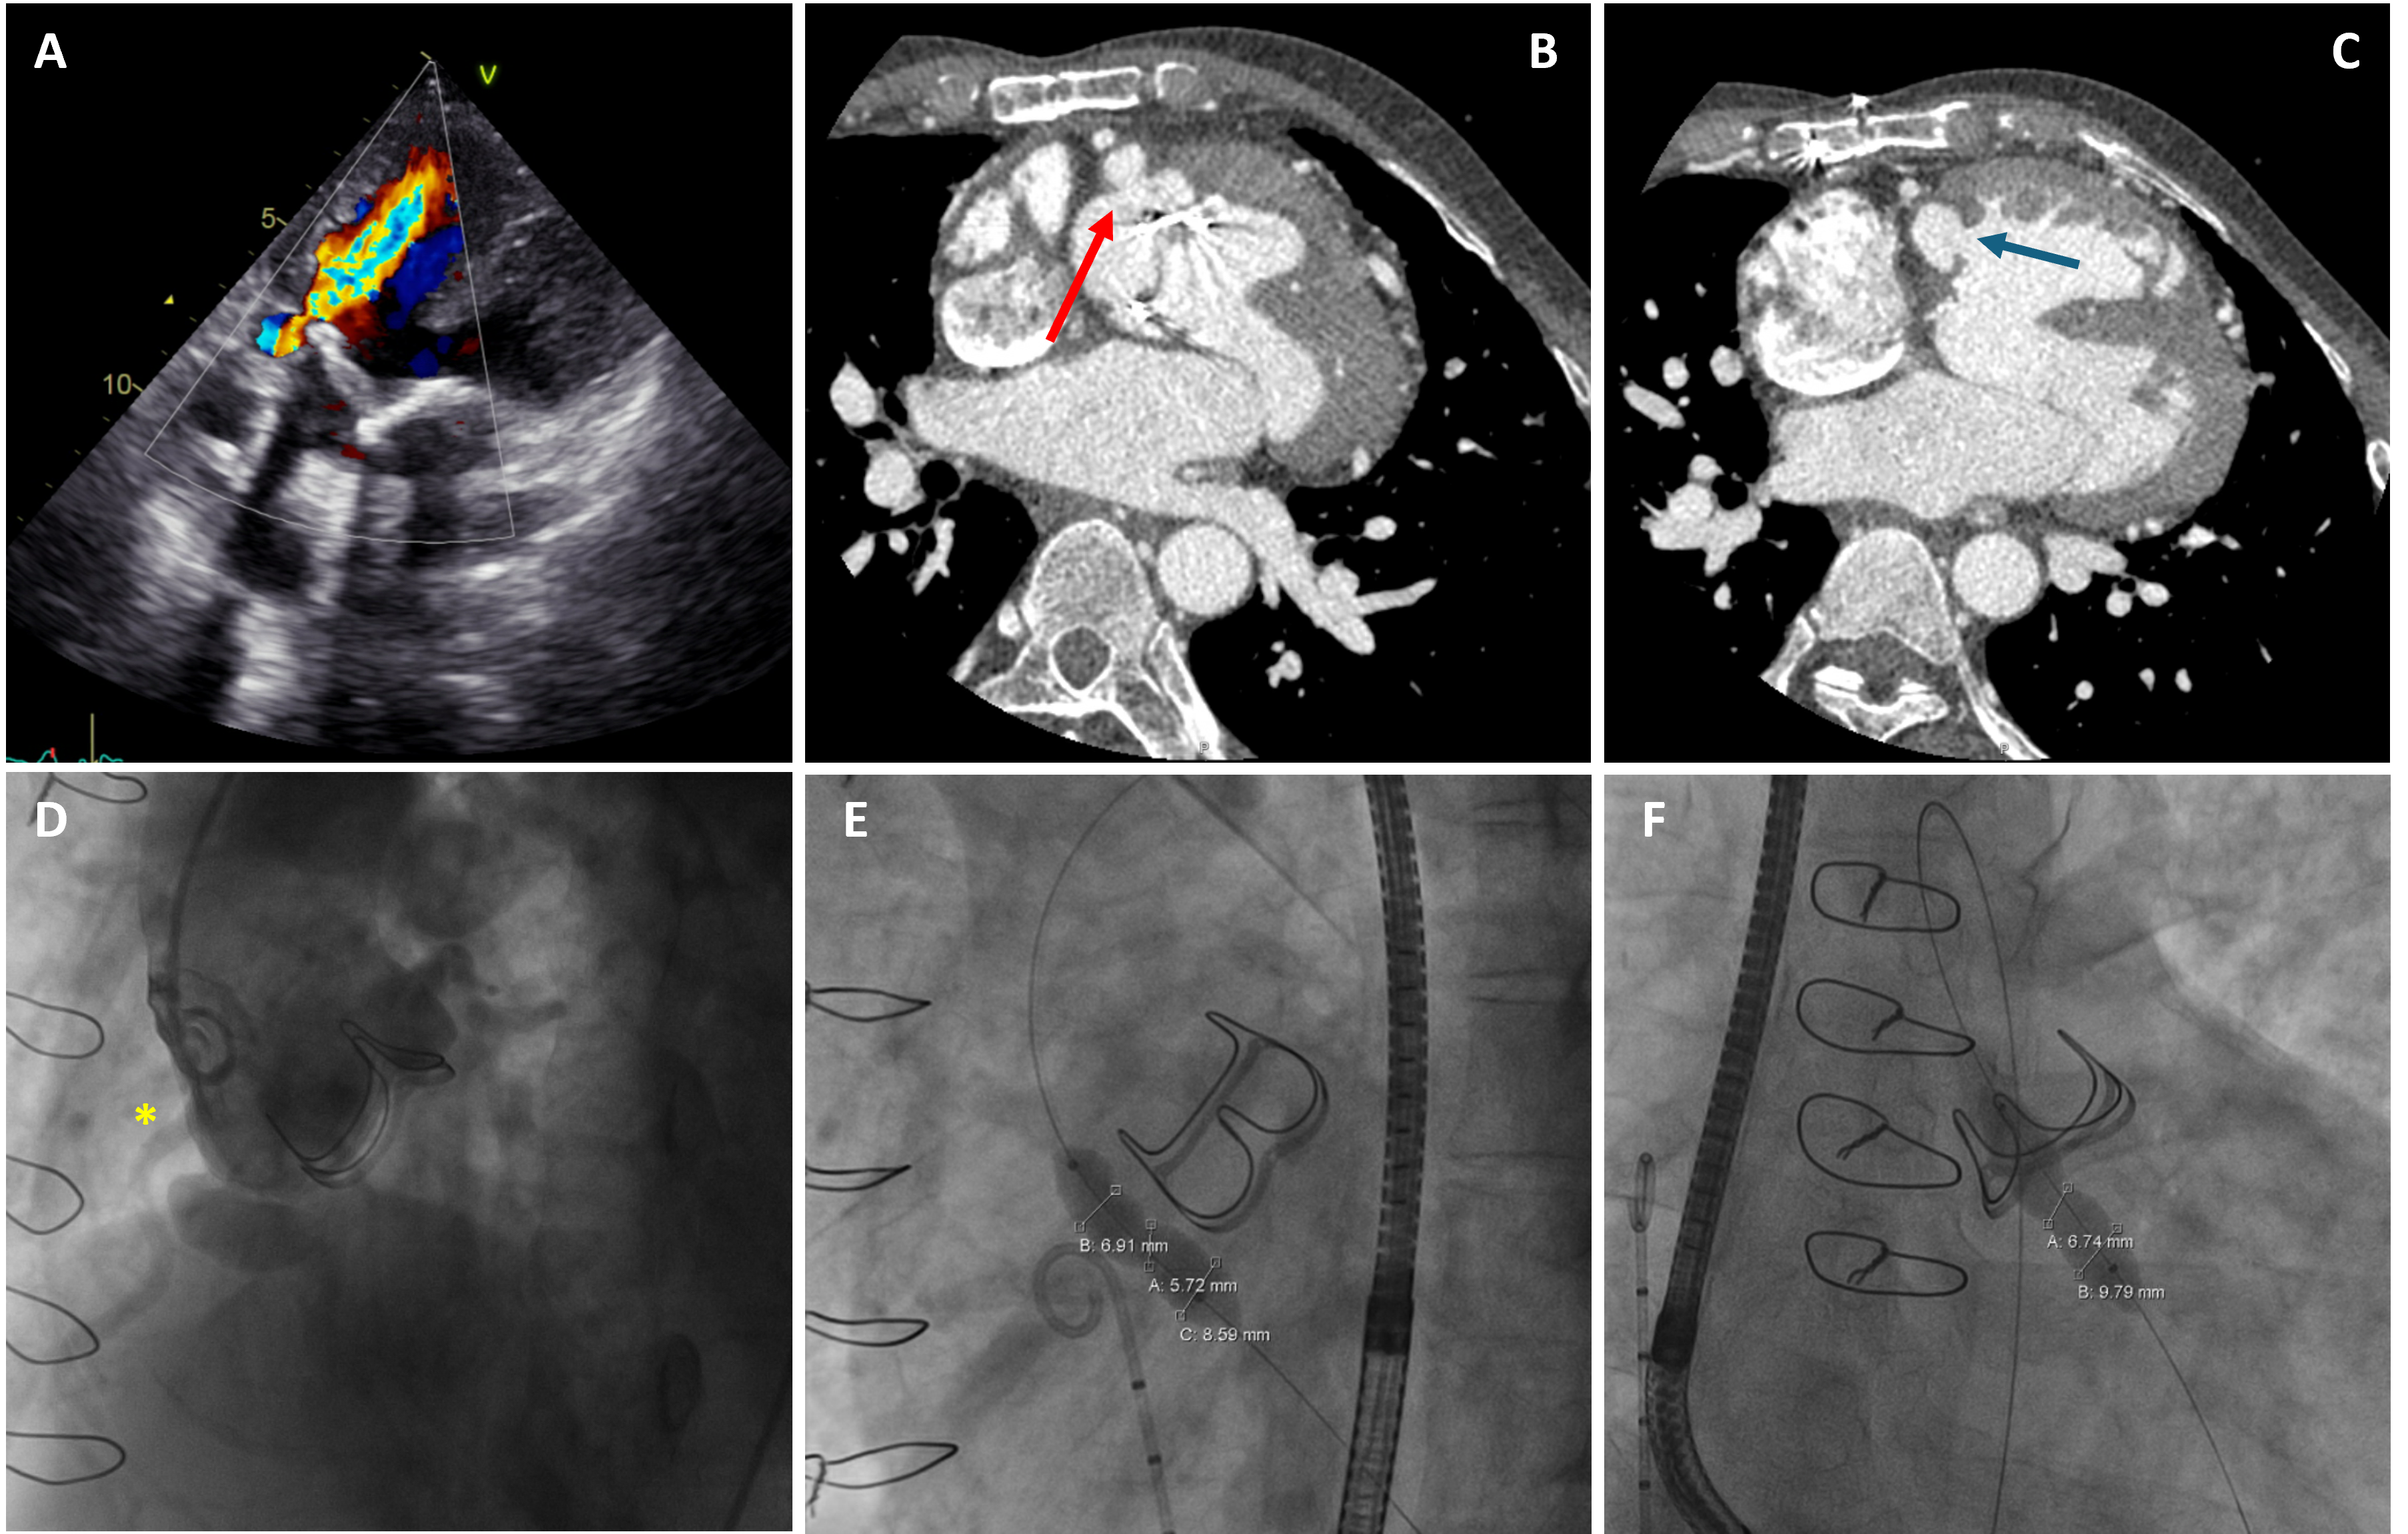

At presentation, transthoracic echocardiography and computed tomography scan confirmed the presence of a perforated RCC aneurysm with diastolic flow into the right ventricle (RV), causing severe aortic paravalvular leak in the context of univentricular physiology, leading to impaired systolic function and exercise tolerance (Figure 1, Video 1). Microbiological workup was unremarkable. In view of the prohibitive surgical risk, transcatheter closure was recommended by the heart team.

The procedure was performed under local anaesthesia under the guidance of transesophageal echocardiography. Balloon sizing confirmed a 6- to 7-mm waist at the communication neck. A 10-mm Amplatzer Vascular Plug II (Abbott) was successfully deployed, achieving complete occlusion of the paravalvular leak (Figure 2, Video 2). Final imaging demonstrated no residual leak. At follow-up, the patient’s exercise tolerance returned to baseline. Imaging showed normalized ventricular function with no residual leak or signs of infection.